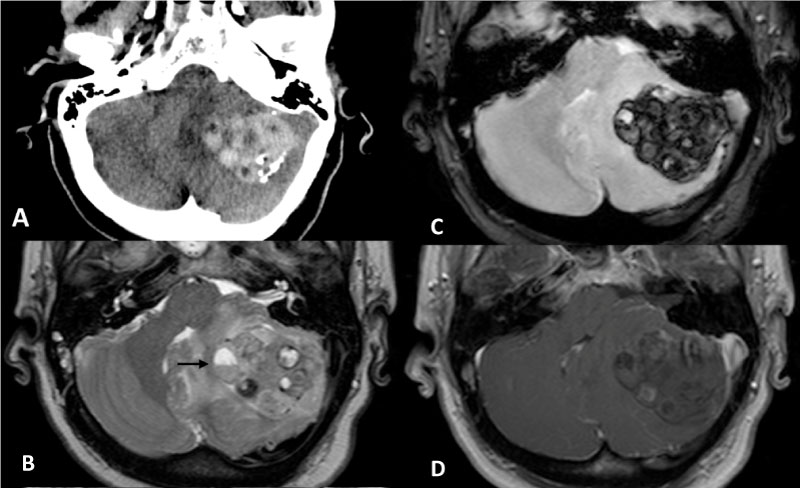

In January 2018, the patient had intense headache, vomiting and rapidly progressive deterioration of the consciousness. An urgent computerized tomography (CT) (Figure 1a) at our hospital revealed a 42 mm hematoma of the left cerebellar hemisphere, with calcifications and perilesional edema, causing compression of the brainstem and triventricular hydrocephalus. Thus, an external ventricular drainage was immediately placed. Magnetic resonance imaging (MRI) (Figure 1b, Figure 1c and Figure 1d) showed a tumor mass of the left cerebellar hemisphere (52 × 33 × 27 mm) with heterogeneous signal due to the presence of peripheral calcifications, diffuse intralesional bleeding, solid nodules and cystic and necrotic components; discrete perilesional edema, severe brainstem compression, triventricular hydrocephalus and herniation of the left cerebellar tonsil were present. DWI, spectroscopy and perfusion sequences did not provide further information because of the diffuse intralesional blood.

Figure 1: a) Computerized Tomography of the skull showing a left cerebellar hemorrhage with small intralesional laminar calcifications; b-d) Magnetic Resonance images depict a left cerebellar multiloculated tumor lesion compressing the brainstem and displacing the 4th ventricle. On T2 and T1WI; b,c) The lesion shows some blood-fluid levels (black arrow), inhomogeneous signal due to blood products in different stages, and vasogenic edema; d) No areas with fat signal are present. The tumor does not enhance after contrast administration. View Figure 1

The MRI appearance of liponeurocytoma is that of a tumor mass of inhomogeneous signal intensity, with isointense areas in both T1W1 and T2Wi, due to high cellular density, hyperintense cysts and spots of hypointensity that indicate areas of calcifications. The presence of focal areas of hyperintensity on T1W1 corresponding to fatty tissue inside the tumor is a characteristic finding found in almost all reported cases and may suggest the preoperative diagnosis of liponeurocytoma [10,12,17]. However, in our own, as in another reported case [12], no areas with fat signal intensity were detected. This may be due to both the scarce amount of tumor cells with lipidic accumulation and the hemorrhage infiltration. The contrast enhancement is slightly inhomogeneous implying mild vascularity [16].